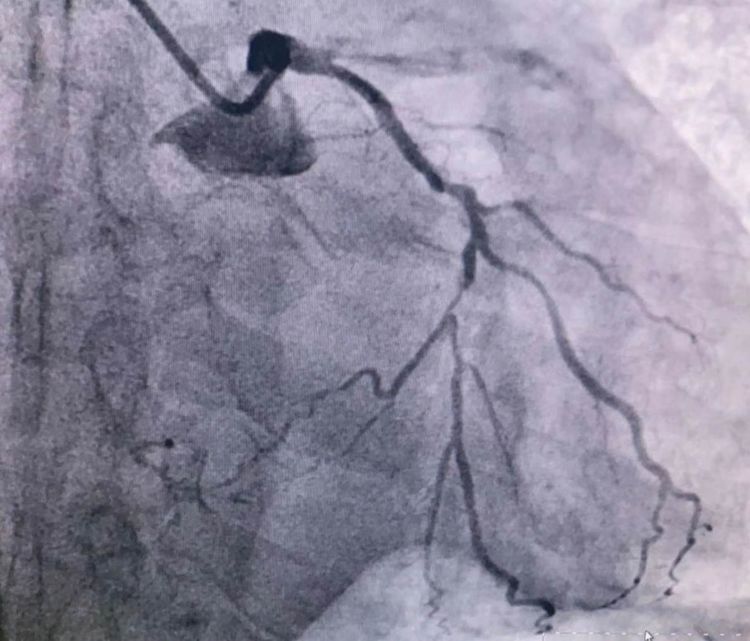

患者前降支、右冠100%閉塞,LCX中段60%狹窄。命懸一線,手術(shù)臺(tái)上持續(xù)胸痛。和患者家屬及時(shí)溝通后,決定行PTCA術(shù)。血壓低至60/40mmHg,在主動(dòng)脈內(nèi)球囊反博的支持下緊急行PCI術(shù)。軌道很快建立,導(dǎo)絲也及時(shí)通過病變血管,噩夢來了,患者發(fā)生室顫了。在吳棟梁院長的指揮下,李陽主任和心臟團(tuán)隊(duì)的成員共同努力下,除顫、冠脈內(nèi)溶栓、多個(gè)球囊輪流上陣,患者病情平穩(wěn)了,罪犯血管及時(shí)開通,血流恢復(fù)三級(jí)血流。平安下臺(tái),準(zhǔn)備擇日再處理冠脈情況。